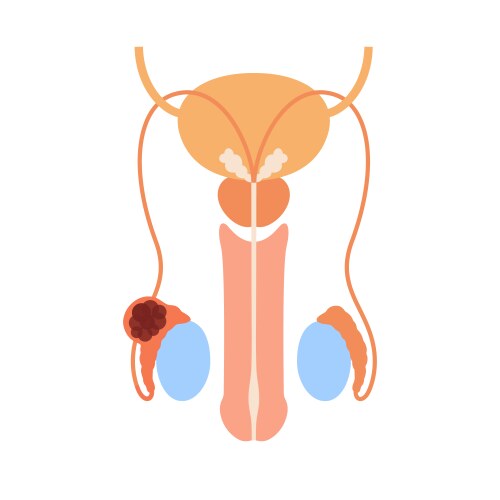

- Urinary

- Prostate

- Bladder

- Body

- Anatomy

- Disease

- Human